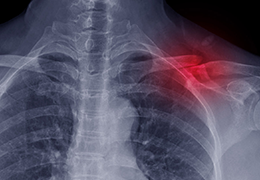

与标准影像处理相比,智能降噪功能可使客户降低辐射剂量,而不会损失影像质量。这在新生儿和儿科成像中尤其重要,在这种情况下以尽可能低的剂量成像至关重要。

提供相配视图选项,以减少所需的曝光次数,并提供更清晰的感兴趣区域视图。